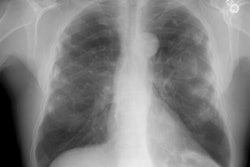

Thesaurosis:

Clinical:

Thesaurosis is associated with the inhalation of hair spray and it is especially common in beauticians. The radiologic features are indistinguishable from sarcoid and some pathologists believe thesaurosis is not an independent entity, but merely sarcoid.